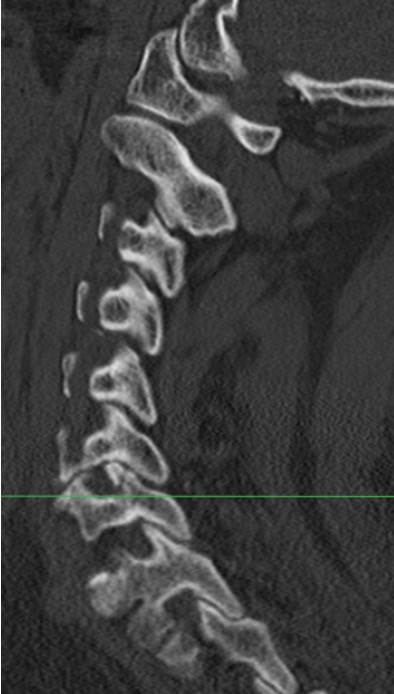

- 37 patients with unilateral facet joint dislocation

- failure of non operative treatment associated with traumatic disc injury

- can develop anterolithesis

- incidence of spinal injury

- 74 patients with unilateral, minimal displaced facet joint fractures

- 15/74 (20%) progressed radiographically (> 10% listhesis)

- only two developed radiculopathy

- risks fractures for instability were initial fracture displacement or presentation with radiculopathy